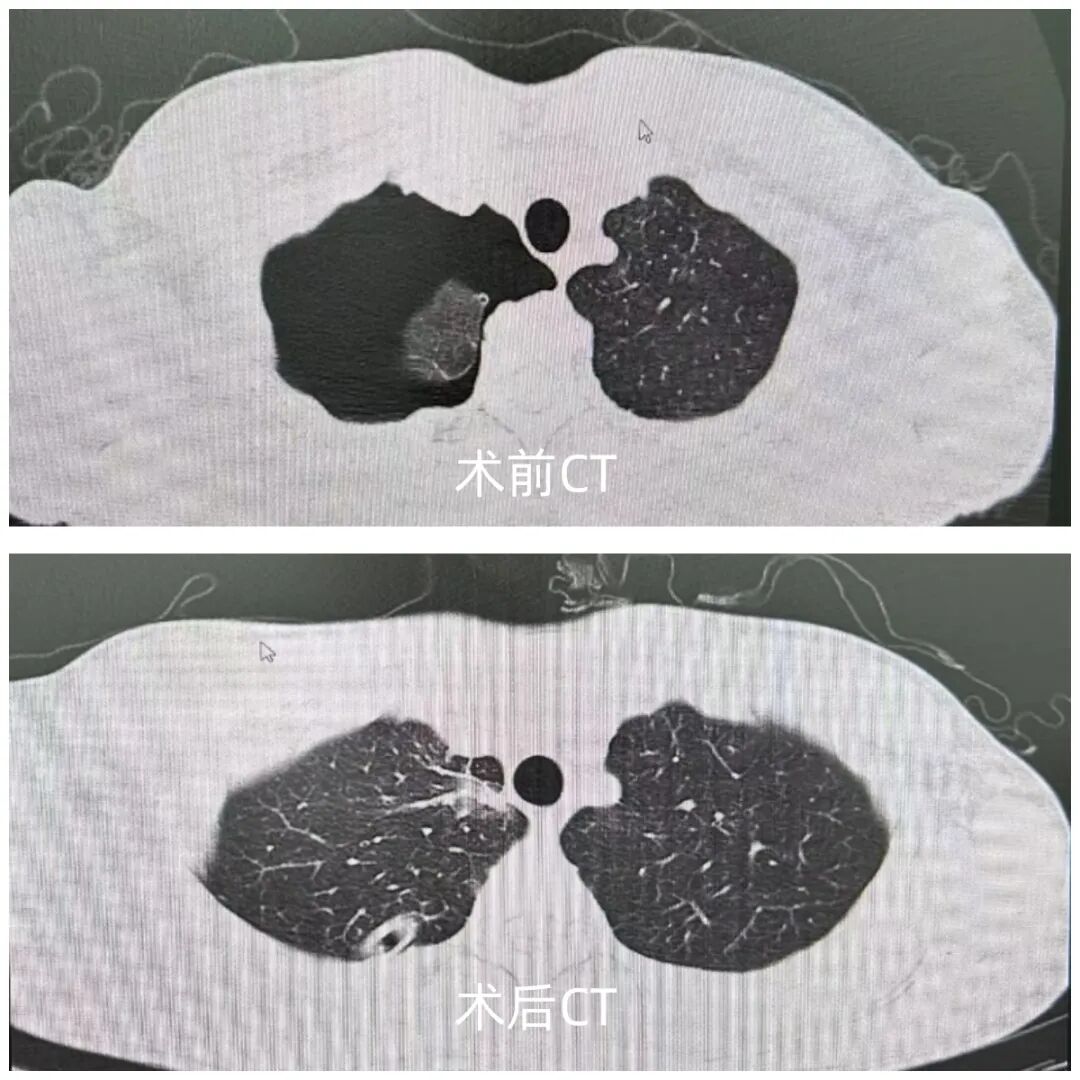

17歲患者張某(化名),突發(fā)胸痛、胸悶4小時(shí)來院就診,經(jīng)檢查確診為“右側(cè)自發(fā)性氣胸”,肺組織壓縮達(dá)60%,患者半年前有右側(cè)自發(fā)性氣胸行胸腔閉式引流病史。自發(fā)性氣胸常見于瘦高體型的青少年,肺大皰破裂是導(dǎo)致自發(fā)性氣胸的病因,單純胸腔閉式引流不能去除肺大皰(病因),所以胸腔閉式引流后氣胸通常會(huì)復(fù)發(fā),手術(shù)切除肺大皰是有效治療方法。

患者入院后胸外科團(tuán)隊(duì)經(jīng)綜合評(píng)估分析,決定采用目前國(guó)內(nèi)領(lǐng)先的“單孔胸腔鏡微創(chuàng)技術(shù)”為患者實(shí)施肺大皰切除及胸膜固定術(shù)。 手術(shù)由我院胸外科楊國(guó)慶主任主刀完成?;颊咝g(shù)后次日即可下床活動(dòng),疼痛輕微,術(shù)后5天順利出院。